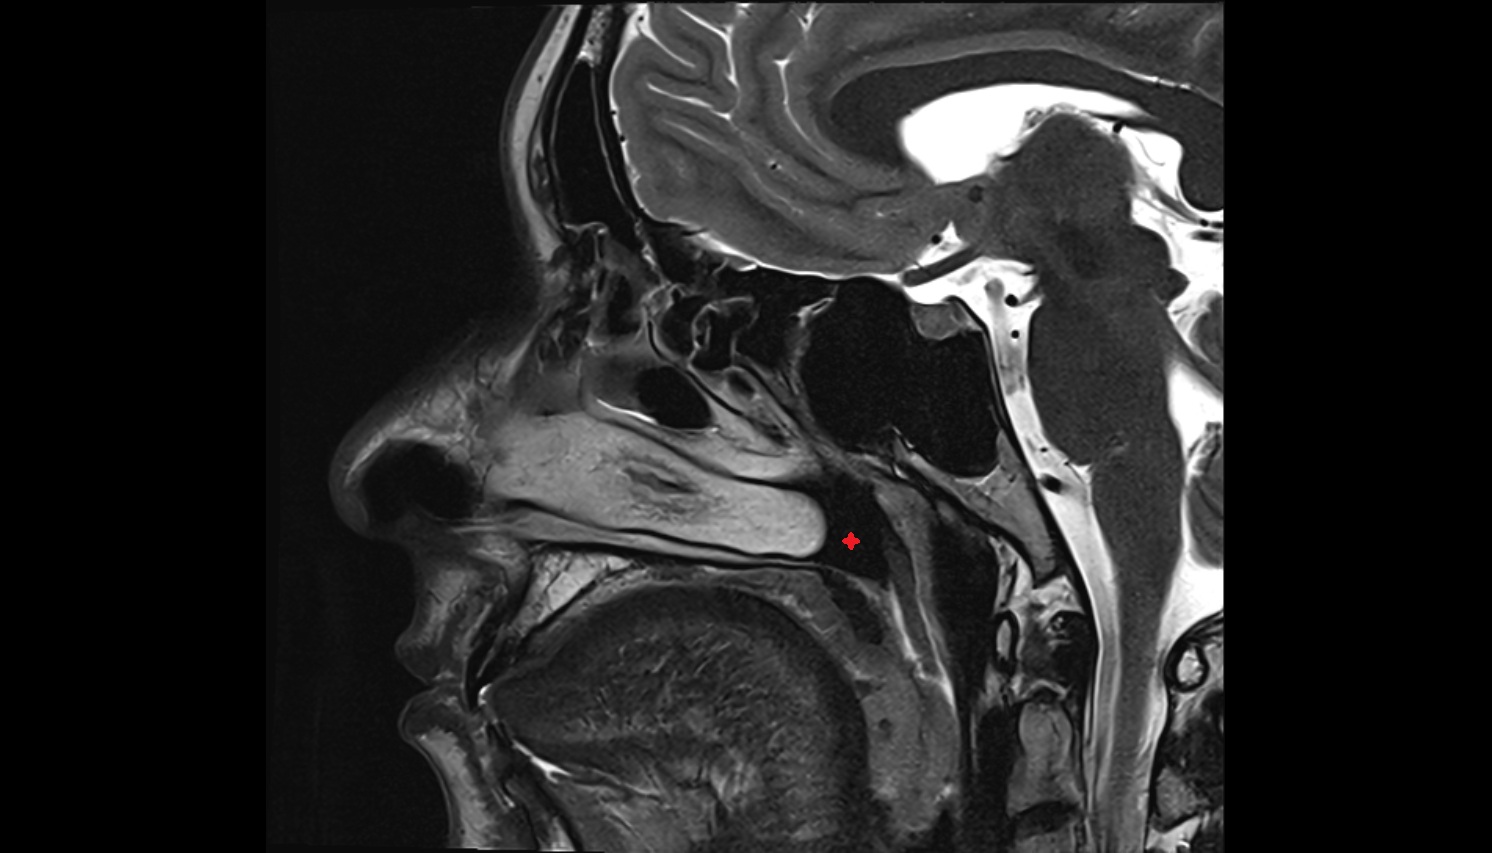

- Temporomandibular joint

- Articular disc of temporomandibular joint

- Articular eminence

- Articular surface of mandibular fossa

- Mandibular condyle

- Mandibular fossa